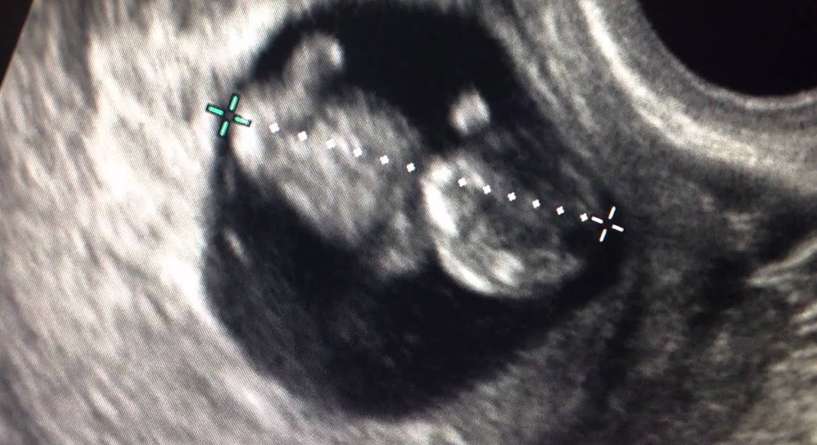

- شكل الجنين في الأسبوع التاسع بالسونار

شكل الجنين في الأسبوع التاسع بالسونار

يصبح شكل الجنين في الاسبوع التاسع بشريا وتطرا عليه التطورات التالية التي سيمكنك ملاحظتها في السونار:

- يصبح وجه الجنين شبيها بالوجه البشري

- يظهر جفنيه

- تنمو أعضاؤه واجهزته الداخلية بالإضافة الى الاعصاب

- يتكون كاحلاه

- تبرز أصابع يديه وقدميه

- تزداد ذراعيه طولا وتنثنيان عند المرفقين

- يتكون الحاجز الفاصل بين الانف والحلق والفم لديه

- تبدا اعضاؤه التناسلية بالظهور